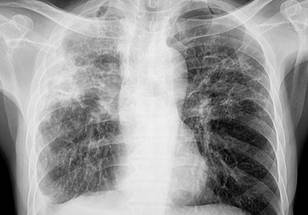

ILD in patients with SSc is usually characterized by bilateral, ground-glass opacities, lower-lobe predominant reticulations, and occasionally honeycombing when seen on high-resolution computed tomography (HRCT). Because mild ILD patients may not exhibit any symptoms in the early stages of the illness, they might not have pulmonary function tests or diagnostic radiography done until they start to express symptoms like dyspnea upon exercise and a persistent cough. On late presentations of ILD, nothing is clear. Thus, the team led by Sabrina Hoa carried out this investigation to describe the incidence, risk factors, and consequences of late-onset SSc-ILD.